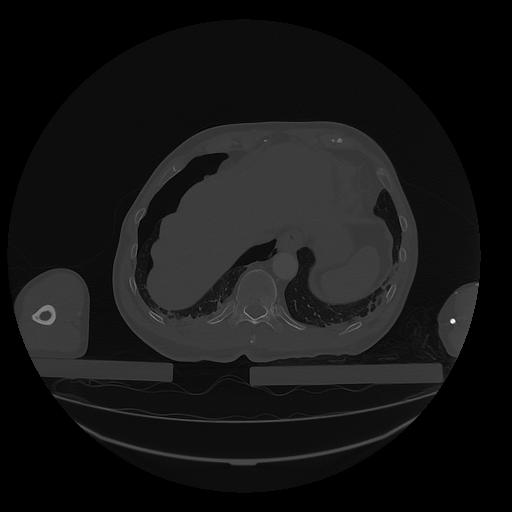

31 PULMON,CE,Vol,1.0,PULMON,,